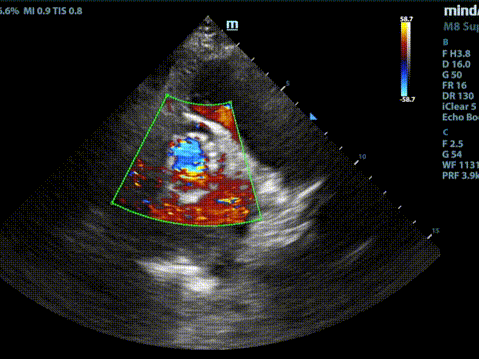

术后经胸超声

释放脱钩后瓣膜形态、位置良好,冠脉血流灌注正常,微量瓣周漏;采用22mm球囊后扩,无压差,无瓣周漏;弓部血管造影未见异常。

术后根部造影

术后压差